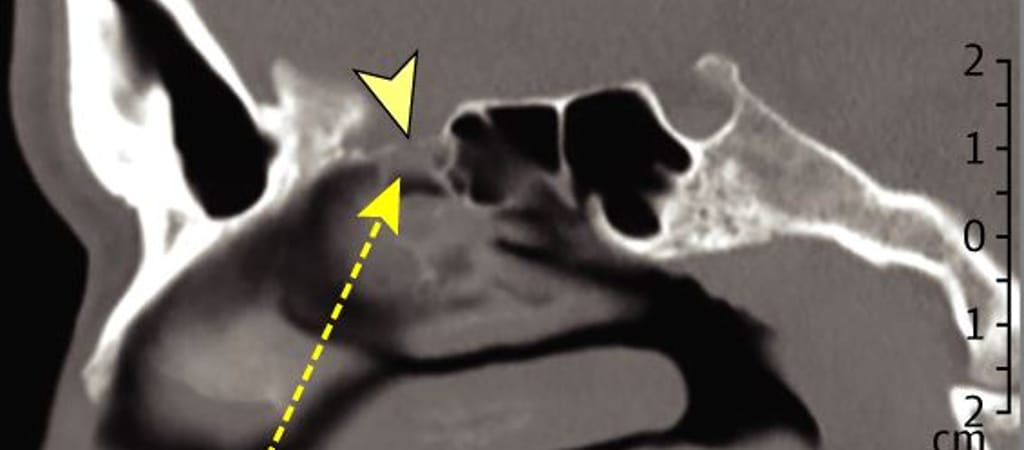

A férfi állapotára egy CT-vizsgálat mutatott rá, amit azt követően végeztek el rajta, hogy felkeresett egy szakrendelőt. A beteg itt részletesen elmesélte, milyen panaszok gyötrik, melyek alapján ő kezdetben egyszerű náthára gyanakodott. A CT-vizsgálatra 9 hónappal a teszt után, tavaly decemberben került sor.

A felvételen jól kivehető volt, hogy férfinak a teszt következtében megsérült a rostacsontja, ami az orrüreg és az agy között található, és szivacsos szerkezetű. A jobb orrlyukból ezért nem valamiféle váladék távozott, hanem agy-gerincvelői, másnéven cerebrospinális folyadék (CSF) – rögzítette a legfontosabb tudnivalókat a JAMA Otolaryngology–Head & Neck Surgery orvosi szakfolyóirat.